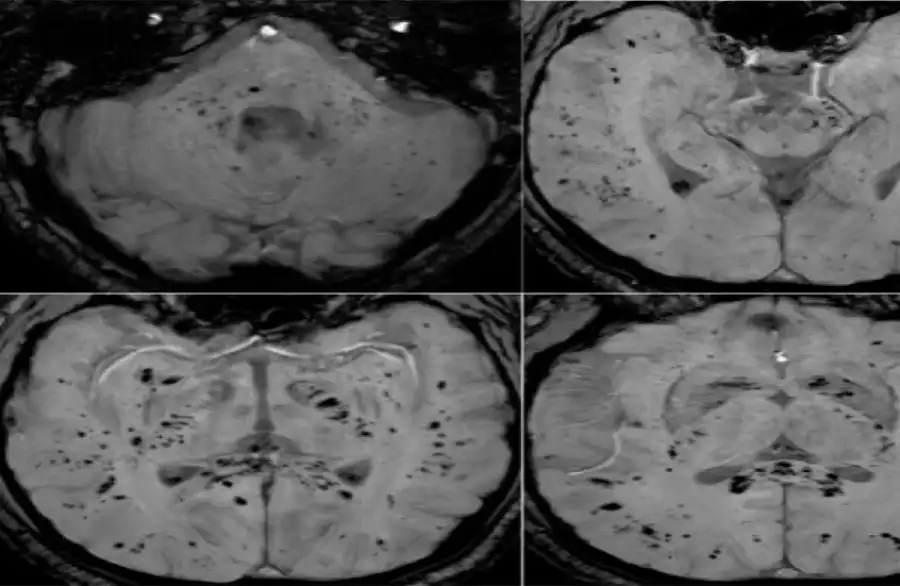

أظهرت دراسة حديثة أجراها علماء في جامعة غريفيث الأسترالية ونُشرت في مجلة Brain, Behavior, & Immunity Health أن فيروس كوفيد-19 لا يؤثر على الجهاز التنفسي فحسب، بل يترك أثرا ملموسا على الدماغ، ويستمر تأثيره حتى لدى الأشخاص الذين يعتبرون أنفسهم متعافين تماما، حتى إذا لم تظهر عليهم أعراض واضحة.وأوضح الباحث الرئيسي الدكتور كيران تاباليا أن الفريق استخدم طرق التصوير بالرنين المغناطيسي متعددة الوسائط لدراسة المادة الرمادية والبيضاء في الدماغ، وهي مهمة للذاكرة والوظائف الإدراكية والصحة العامة للدماغ. ووجد الباحثون اختلافات ملحوظة في أنسجة الدماغ وموادها الكيميائية العصبية وشدة الإشارة وبنية الأنسجة لدى المتعافين من كوفيد-19، حتى في حالات الإصابة التي اعتبرت بسيطة.

وأضاف تاباليا: "تبين أن التغيرات في أنسجة الدماغ مرتبطة بشدة الأعراض"، ما قد يفسر مشكلات إدراكية طويلة الأمد مثل تدهور الذاكرة والتركيز، والتي قد تستمر لشهور أو حتى سنوات بعد الإصابة.وتشير النتائج إلى العواقب العصبية طويلة المدى للفيروس، وهو ما أكدته أيضا منظمة الصحة العالمية، التي أعلنت مؤخرا أن الأعراض طويلة الأمد بعد كوفيد-19 لا تزال مشكلة خطيرة تؤثر على عدد كبير من الناس.